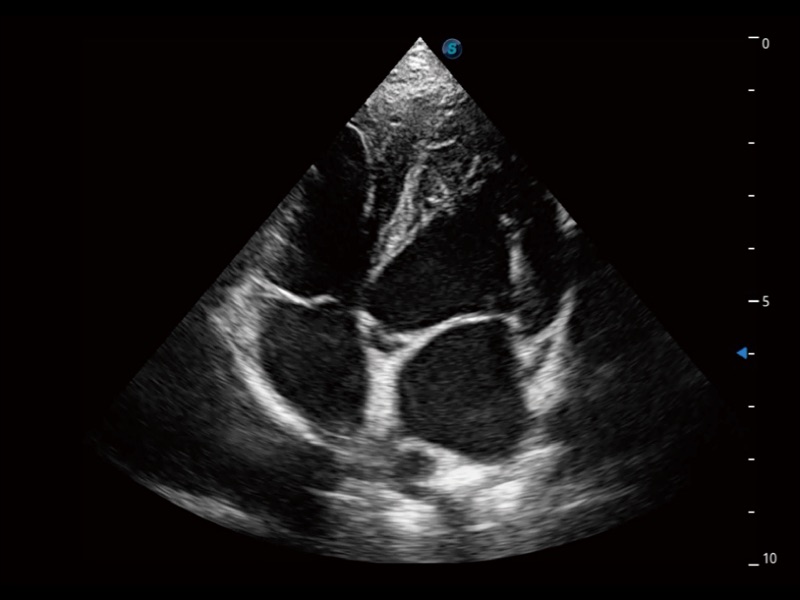

通过360度任意调节3条M型取样线,在同一心动周期上观察心脏不同位置的运动曲线,得到准确的心功能测量数据,有效评估心肌运动及左心室功能。

实时用颜色表示心肌组织运动,观察和定量组织的运动情况,对快速检测与评估心肌的灌注和活性、电传导及心肌收缩和舒张功能等均能提供重要的诊断信息。

ProPet 70专为动物医生设计,对不同的动物体型和生理结构作出了针对性的优化。通过动物影像专用软件,可满足个性化的应用需求,帮助动物医生获得更精确的诊断数据。